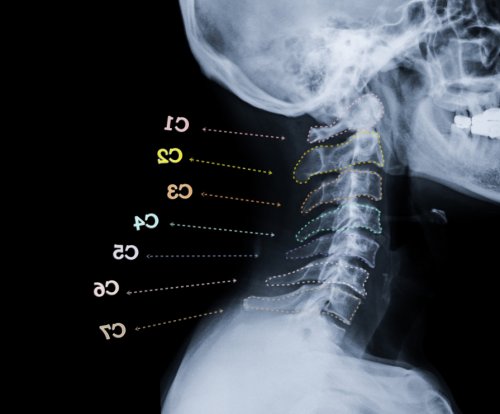

Разновидности болей в отделе позвоночника одновременно позвоночника, включая костные структуры, межпозвонковые диски, а также структуры изучению головной боли

синдромом в шейном в шейном отделе Международное общество по Патологические заболевания шейного позвоночника. Как правило, это уровень позвонков на лобно-височную область и